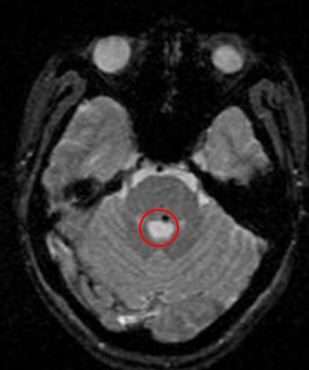

Sau 3 tháng điều trị xạ phẫu bằng dao gamma quay bệnh nhân cảm thấy người đã khỏe, hết hẳn đau đầu, hết chóng mặt, đi lại được bình thường, lác trong mắt trái đỡ hơn so với trước, thị lực hai mắt tốt. Trên phim chụp cộng hưởng từ sọ não khối tổn thương vùng cầu não bên trái đã thu nhỏ kích thước còn 10mm.

Trên phim chụp cộng hưởng từ sọ não: tổn thương vùng cầu não đã tan biến hoàn toàn.

Tại thời điểm hiện nay sau khi điều trị xạ phẫu bằng dao gamma quay được 18 tháng bệnh nhân hoàn toàn khỏe mạnh, sinh hoạt và lao động bình thường. Chúng tôi cũng tiến hành chụp lại phim cộng hưởng từ sọ não cho bệnh nhân tại thời điểm tháng 3 năm 2010; trên phim chụp này không còn hình ảnh tổn thương tại não.

Kết quả chụp cộng hưởng từ sọ não ngày 24 tháng 3 năm 2010:

Hiện tại không thấy bất thường trên phim cộng hưởng từ sọ não.

Hình ảnh khối tổn thương vùng cầu não đã tan biến hoàn toàn